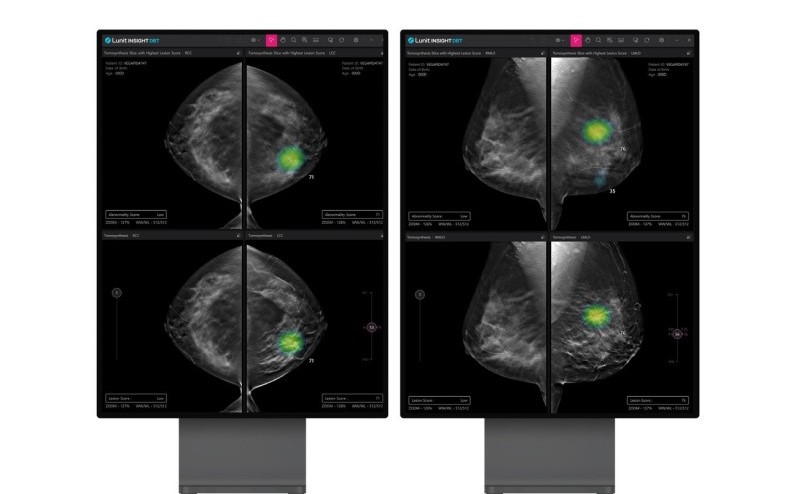

‘루닛 인사이트 DBT’는 유방암 진단용 3차원 영상을 AI(인공지능) 기반으로 분석해 의료진의 진단을 보조하는 제품이다.

루닛 인사이트 DBT는 기존 2차원 유방촬영술보다 정확한 진단이 가능하고, 한국을 비롯한 동양 여성에서 흔히 발견되는 치밀 유방에 대한 정밀진단을 제공할 수 있다는 장점을 갖췄다.

지난해 말 열린 북미영상의학회(RSNA)에서 미국 에모리대학교병원 연구팀이 발표한 연구에 따르면 루닛 인사이트 DBT의 AI 모델 성능 지표(AUC)는 0.92를 기록하며 뛰어난 성능을 입증했다.

인종, 민족, 연령, 유방 밀도 등 다양한 변수가 있는 환경에서 고성능을 유지했다. 석회화와 같이 비교적 판독하기 어려운 병변 유형에서도 높은 진단 성능을 나타냈다.